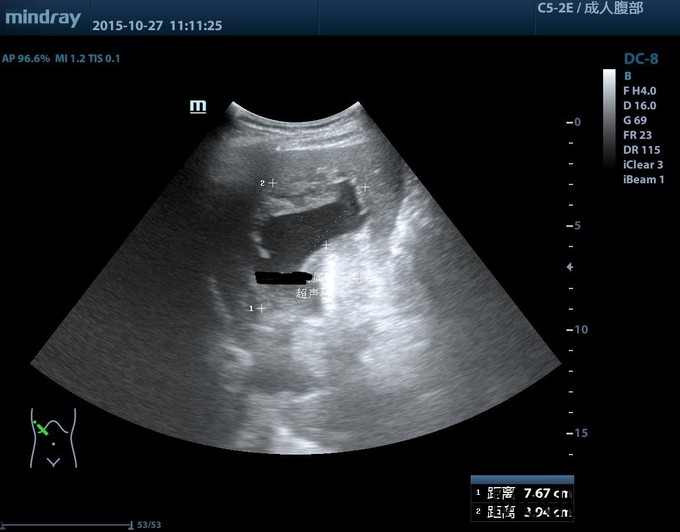

老年男性患者,1年前因腹部膨隆查腹部B超发现肝囊肿,最大直径约21cm,于香港门诊治疗,建议密切随访。近期诉腹胀较前加重,超声示囊肿较前增大。患者无腹痛,无返酸,无发热、黄疸,无呕血,无黑便。既往高血压病20余年,服药控制良好。现为进一步手术治疗入院。

查体: 皮肤黏膜无黄染及苍白,腹部膨隆,腹肌软,未触及肝脏肋下缘,无肝震颤。 辅查: 1.腹部CT:1.肝内多发囊肿,其中右叶可见巨大囊肿。 2.胆囊结石。 3.右肾小囊肿;左肾小结石。 2.术后病检: 1(胆囊)送检5.5x2x1cm组织一块,内见结石。镜下:慢性胆囊炎,胆囊结石。2(囊壁)送检直径6cm囊壁样组织一块,囊壁厚0.1cm。 镜下:送检纤维囊壁样组织,部分囊壁披覆单层上皮,局部囊壁可见少量肝组织,病变符合肝囊肿。

诊断:1.肝内多发囊肿 2.胆囊结石 治疗:完善术前准备,未见明显禁忌,且患者强烈要求美观、微创,遂决定在气管内麻下行机器人辅助下肝囊肿开窗引流+囊肿切除+胆囊切除术。手术过程顺利,术中病情平稳。术后安返病房,给予禁食、心电监护、吸氧、肠外营养、止血等对症支持治疗。